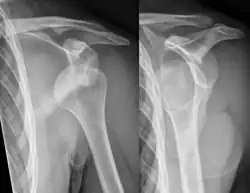

X-ray at left shows anterior dislocation in a young man. X-ray at right shows the same shoulder after reduction and internal rotation, revealing a Bankart lesion and a Hill-Sachs lesion.

In over 95% of shoulder dislocations, the humerus is displaced anteriorly.[8] In most of those, the head of the humerus comes to rest under the coracoid process, referred to as sub-coracoid dislocation. Sub-glenoid, subclavicular, and, very rarely, intrathoracic or retroperitoneal dislocations may also occur.[9]

Anterior dislocations are usually caused by a direct blow to, or fall on, an outstretched arm. The person typically holds his/her arm externally rotated and slightly abducted.[10]

A Hill–Sachs lesion is an impaction of the head of the humerus left by the glenoid rim during dislocation.[6] Hill-Sachs deformities occur in 35–40% of anterior dislocations. They can be seen on a front-facing X-ray when the arm is in internal rotation.[11] Bankart lesions are disruptions of the glenoid labrum with or without an avulsion of bone fragment.[12]